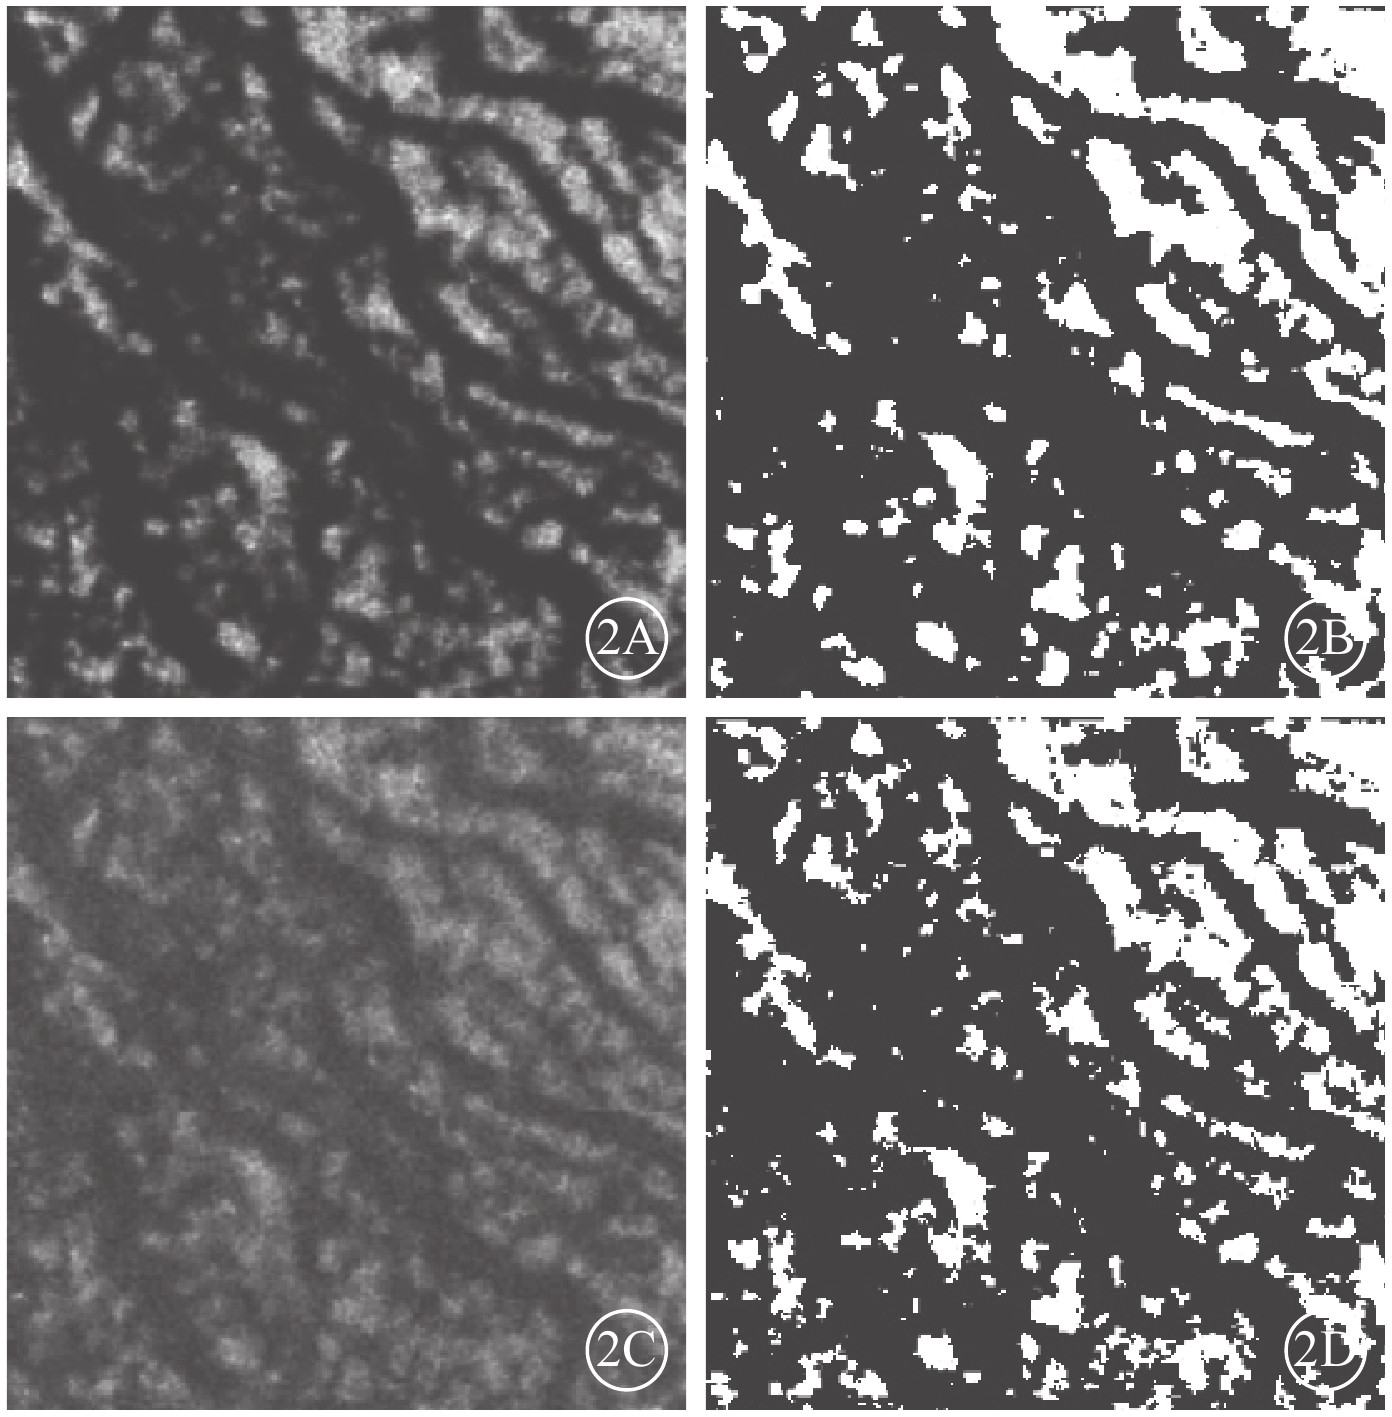

Bruch膜下1/2脈絡膜厚度層面,SS-OCTA圖像呈現與平面(en-face)OCT所示脈絡膜大血管分布較為一致的黑色血流信號,經二值化處理后所得的黑白圖像能反映脈絡膜大血管層的高速血流分布(圖2)。ECS組受檢眼脈絡膜SS-OCT和脈絡膜大血管層SS-OCTA表現為個別脈絡膜大血管極度擴張、高速血流匯聚和脈絡膜大血管普遍擴張、高速血流彌漫分布兩種類型。13只眼中,個別脈絡膜大血管極度擴張、高速血流匯聚6只眼;脈絡膜大血管普遍擴張、高速血流彌漫分布7只眼(圖3),其中1只眼為漿液性脈絡膜視網膜病變。對照組受檢眼脈絡膜SS-OCT無明顯大血管擴張征象,脈絡膜大血管層SS-OCTA圖像顯示高速血流分散而細小(圖4)。ECS組、對照組受檢眼脈絡膜大血管層FBFD分別為(76.35±14.46)%、(63.57±13.42)%;兩組受檢眼脈絡膜大血管層FBFD比較,差異有統計學意義(t=2.775,P=0.01)。

圖2

對照組黃斑區脈絡膜大血管層en-face SS-OCTA像及en-face OCT像。2A. SS-OCTA像;2B. 二值化處理后的SS-OCTA像;2C. en-face OCT像;2D. 二值化處理后的en-face OCT像。en-face SS-OCTA獲得的高速血流分布與en-face OCT獲得的血管分布具有較好的一致性

圖2

對照組黃斑區脈絡膜大血管層en-face SS-OCTA像及en-face OCT像。2A. SS-OCTA像;2B. 二值化處理后的SS-OCTA像;2C. en-face OCT像;2D. 二值化處理后的en-face OCT像。en-face SS-OCTA獲得的高速血流分布與en-face OCT獲得的血管分布具有較好的一致性

Bruch膜下1/2脈絡膜厚度層面,SS-OCTA圖像呈現與平面(en-face)OCT所示脈絡膜大血管分布較為一致的黑色血流信號,經二值化處理后所得的黑白圖像能反映脈絡膜大血管層的高速血流分布(圖2)。ECS組受檢眼脈絡膜SS-OCT和脈絡膜大血管層SS-OCTA表現為個別脈絡膜大血管極度擴張、高速血流匯聚和脈絡膜大血管普遍擴張、高速血流彌漫分布兩種類型。13只眼中,個別脈絡膜大血管極度擴張、高速血流匯聚6只眼;脈絡膜大血管普遍擴張、高速血流彌漫分布7只眼(圖3),其中1只眼為漿液性脈絡膜視網膜病變。對照組受檢眼脈絡膜SS-OCT無明顯大血管擴張征象,脈絡膜大血管層SS-OCTA圖像顯示高速血流分散而細小(圖4)。ECS組、對照組受檢眼脈絡膜大血管層FBFD分別為(76.35±14.46)%、(63.57±13.42)%;兩組受檢眼脈絡膜大血管層FBFD比較,差異有統計學意義(t=2.775,P=0.01)。

圖2

對照組黃斑區脈絡膜大血管層en-face SS-OCTA像及en-face OCT像。2A. SS-OCTA像;2B. 二值化處理后的SS-OCTA像;2C. en-face OCT像;2D. 二值化處理后的en-face OCT像。en-face SS-OCTA獲得的高速血流分布與en-face OCT獲得的血管分布具有較好的一致性

圖2

對照組黃斑區脈絡膜大血管層en-face SS-OCTA像及en-face OCT像。2A. SS-OCTA像;2B. 二值化處理后的SS-OCTA像;2C. en-face OCT像;2D. 二值化處理后的en-face OCT像。en-face SS-OCTA獲得的高速血流分布與en-face OCT獲得的血管分布具有較好的一致性